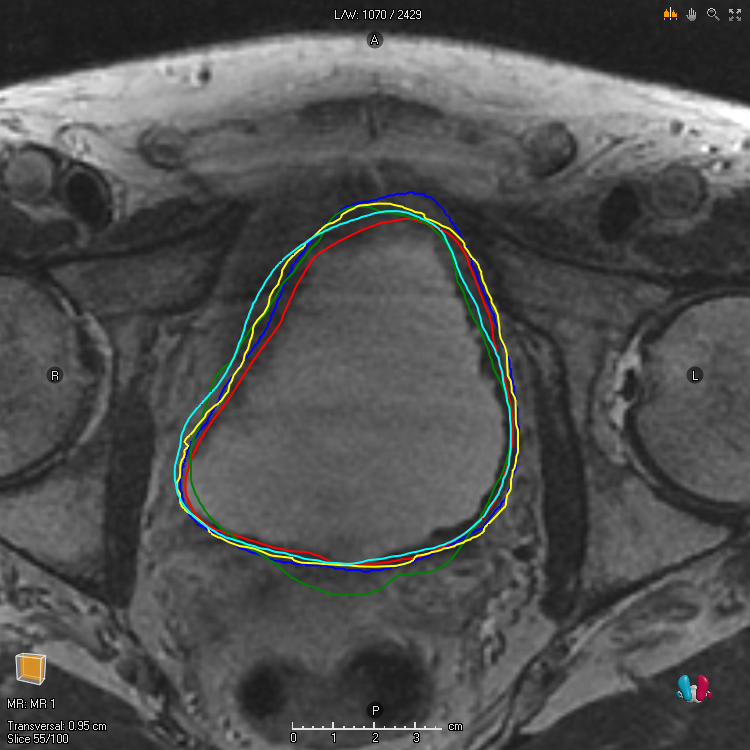

For a noisy segmentation , that is, a random variable taking values in , can be taken to be the exact marginal success probability . Such marginal functions are important in theory but can rarely be obtained in practice. Alternative choices of marginal functions include finite sample approximations, that is, point-wise averages over finite observations of , and estimates of according to a single annotator [15, 11, 31, 16, 17]. These choices of are important because they are sometimes used for training machine learning models. Finally, note that and is a common alternative way of specifying the metric. For Dice, this sort of relationship does not hold in general . However, it does hold that when the volume of the noisy labels is constant , and it holds approximately when the variance of the volume of the noisy labels is small , which is often the case in medical image segmentation applications. Examples of observations of a particular for a couple of different target structures are depicted in Figure 1.

For our experiments we investigate two data sets. The first data set (G) contains segmentations in the pelvic area and is part of the Gold Atlas project [25]. The data is in 3D with a resolution of pixels per slice and consist of patients with different ROI’s (region of interest), each of which have been delineated by experts (see Figure 1 for an illustration of the segmentations associated with two different ROI’s for one patient). The second data set (L) contains segmentations in the thorax area and is part of The Lung Image Database Consortium (LIDC) and Image Database Resource Initiative (IDRI) [1] and is hosted by TCIA [7]. The data is in 3D with a resolution of pixels per slice and contains cases with lung nodules delineated by experts. For each data set, ROI and patient, a marginal function is formed by taking the fraction of which each pixel has been selected by the annotators, that is, a finite sample approximation is considered. The resulting marginal functions are then used to compute the segmentations (19) and (20). For (G) we make use of the software Plastimatch [30] and for (L) we make use of the python package pylidc [12]. Details on the experiments can be found in the Supplementary Document. Code and instructions on how to reproduce the experiments can be found at https://github.com/marcus-nordstrom/optimal-solutions-to-accuracy-and-dice.